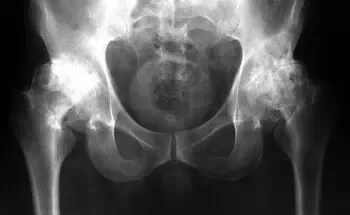

Поїхала в районну лікарню до Львова, там мені зробили недешеве обстеження. Через кілька годин результати були готові, і мій лікар сказав: “Чому ви ігнорували симптоми раніше? У вас артроз! Ви його запустили до 2 стадії. Якщо хочете не стати інвалідом, вам потрібно робити операцію на стегні та колінах!”

(ренген знімки моїх колінних та тазових суглобів)